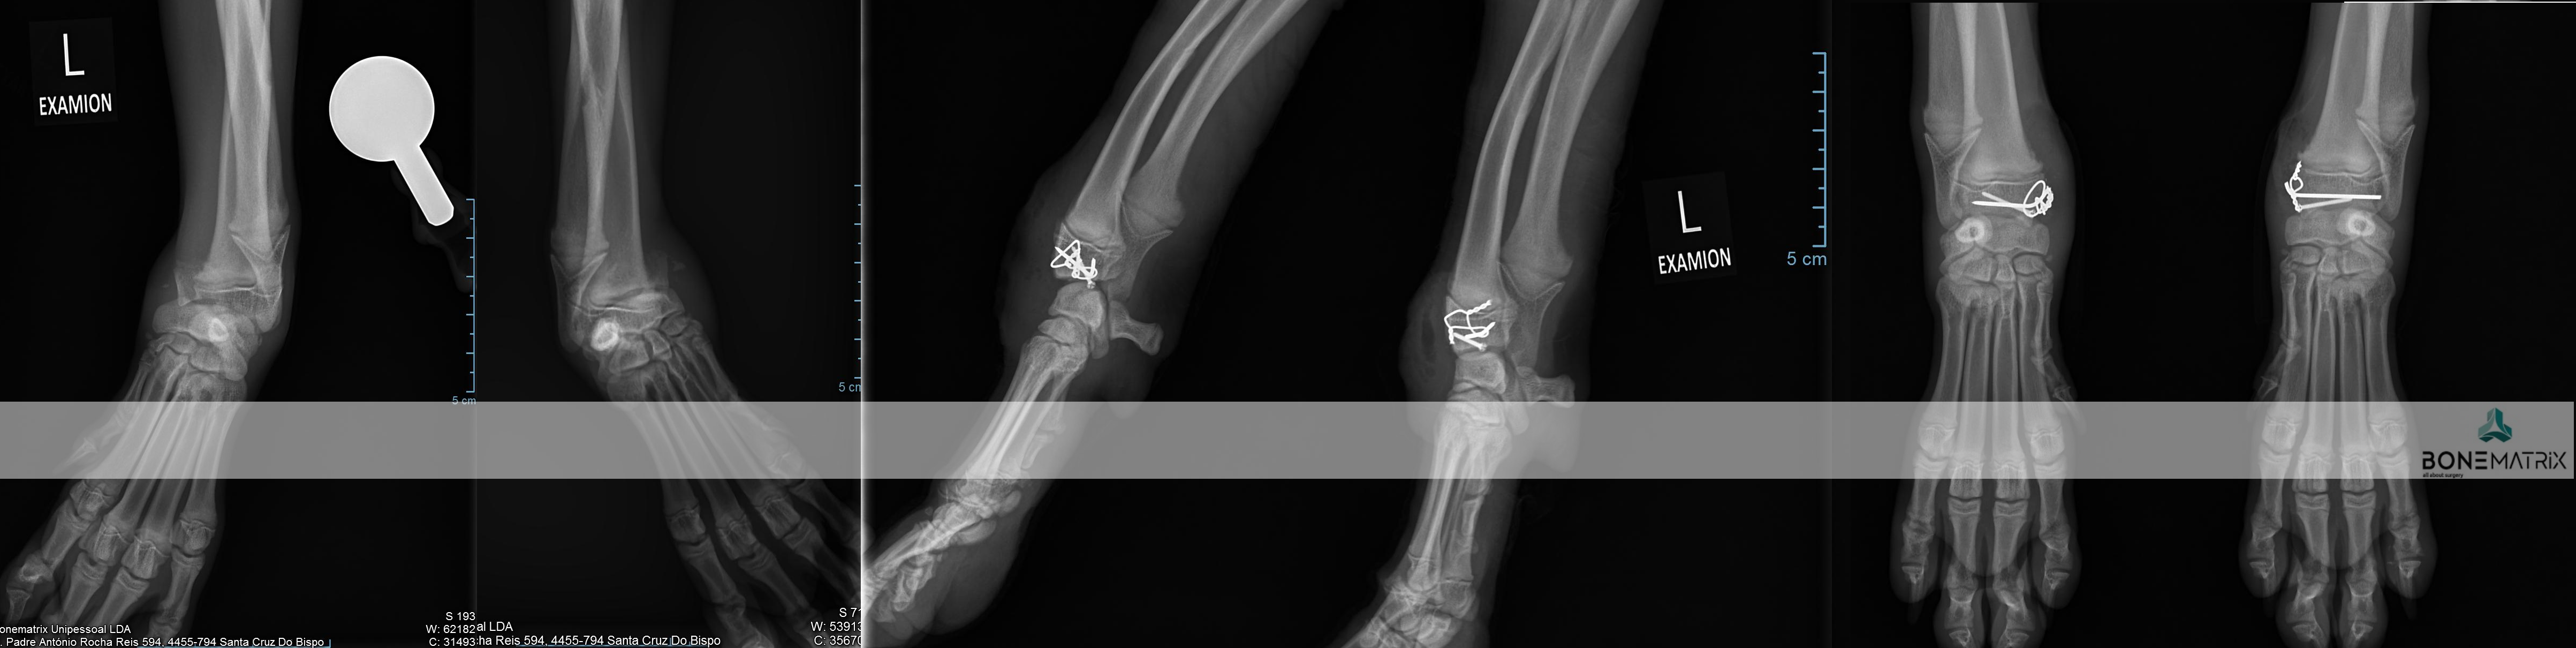

O que é?

As deformidades angulares são patologia que podem assumir as mais variadas apresentações.

A sua origem pode estar relacionada com fatores genéticos, traumas sofridos durante a imaturidade do animal, pode apresentar-se como uma doença de desenvolvimento e pode também ter influências ambientais ou nutricionais.

Todas elas se caracterizam-se por um desvio na correta forma de um determinado osso ou membro.

Que consequências podem surgir da apresentação de uma deformidade angular?

As consequências da apresentação de deformidades angulares estão em muito relacionadas com a localização destas e com a exuberância da apresentação.

Estes desvios da conformação normal podem provocar desde osteoartrite articular ou laxitude dos mecanismos de estabilização de articulações até incapacidade na realização da marcha do animal afetando severamente a qualidade de vida deste.

Como diagnosticar/ Sinais?

O diagnóstico é realizado por meio de análise clinica da anatomia dos membros e é estudada por norma através da realização de um estudo radiográfico.

O animal poderá ser desde assintomático a apresentar sintomas que passam por claudicação, lesões em estruturas articulares consequentes destes desvios angulares, incapacidade na realização de determinados movimentos até incapacidades severas de mobilidade.

A realização de um estudo radiográfico é imprescindível para definição de um planeamento cirúrgico de correção.

Em casos mais complexos pode ser necessário o recurso a estudos de imagem avançada, tanto para o estudo da deformidade como para a produção de instrumentos de cirurgia (guias de corte 3D, produção de placas com customizadas) para que seja realizada a cirurgia com precisão.

Qual o tratamento indicado?

O tratamento depende sempre da forma da patologia apresentada.

Por norma envolve realização de cortes ósseos, definidos com determinada angulação para que seja corrigida a deformidade angular, com subsequente estabilização da fratura induzida com a utilização de placas e parafusos bloqueados (sistema que oferece a maior segurança para a estabilização de fraturas).